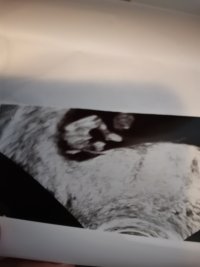

11+3

. Jeg blir helt i oppløsning av å tenke på at han ikke får bli bestefar. Jeg hadde jo egentlig termin i mars og kssnkke det kunne gått liksom. Men men. Sånn er det jo ikke mer.